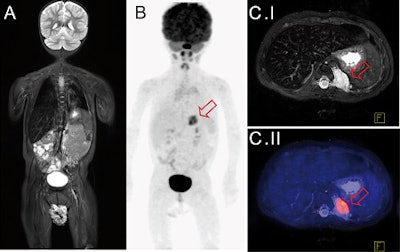

Two pairs of readers analyzed the PET/CT and PET/MRI results separately and independently. They found a total of 21 areas of focal FDG uptake in seven scans of six patients in both PET/CT and PET/MRI. The median lesion size was 14 ± 9 mm.

With PET/CT, seven suspicious lesions in four patients were identified as PET-negative, whereas PET/MRI found eight suspicious PET-negative lesions in five patients. The median lesion size was 10 ± 12 mm.

Of seven lesions that were interpreted differently by PET/CT and PET/MRI, six were PET-positive and had a clearer morphologic correlate in MRI compared to CT.

Most importantly, five of 10 PET/MRI scans lead to potential changes in patient management, compared with PET/CT.

"This additional examination [based on PET/CT] became unnecessary after PET/MRI, where local imaging was performed together with whole-body staging in one single examination," the authors wrote. "In one patient, the detection of a suspicious morphological MR correlate for focal tracer accumulation initiated close follow-up imaging and extended treatment."